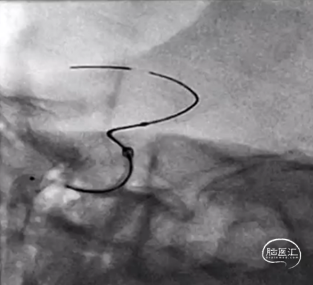

2.Nuva®密网支架输送系统的释放-回收段显影设计,术中可准确快速指示出释放-可回收区域,区间显影设计极大地方便了术中的操作,有助于支架的成功释放。

3.Nuva®密网支架具有较好的柔顺性,释放于迂曲的血管中,可以很好地顺应血管形态,术中打开顺畅,贴壁良好,径向支撑力适中,推挤过程也不易折弯变形;支架整体显影设计,透视效果优异,术中很容易观察支架的打开、走形及贴壁情况。